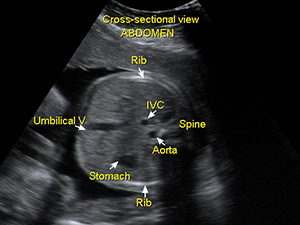

腹部

胎兒肚子之橫切面